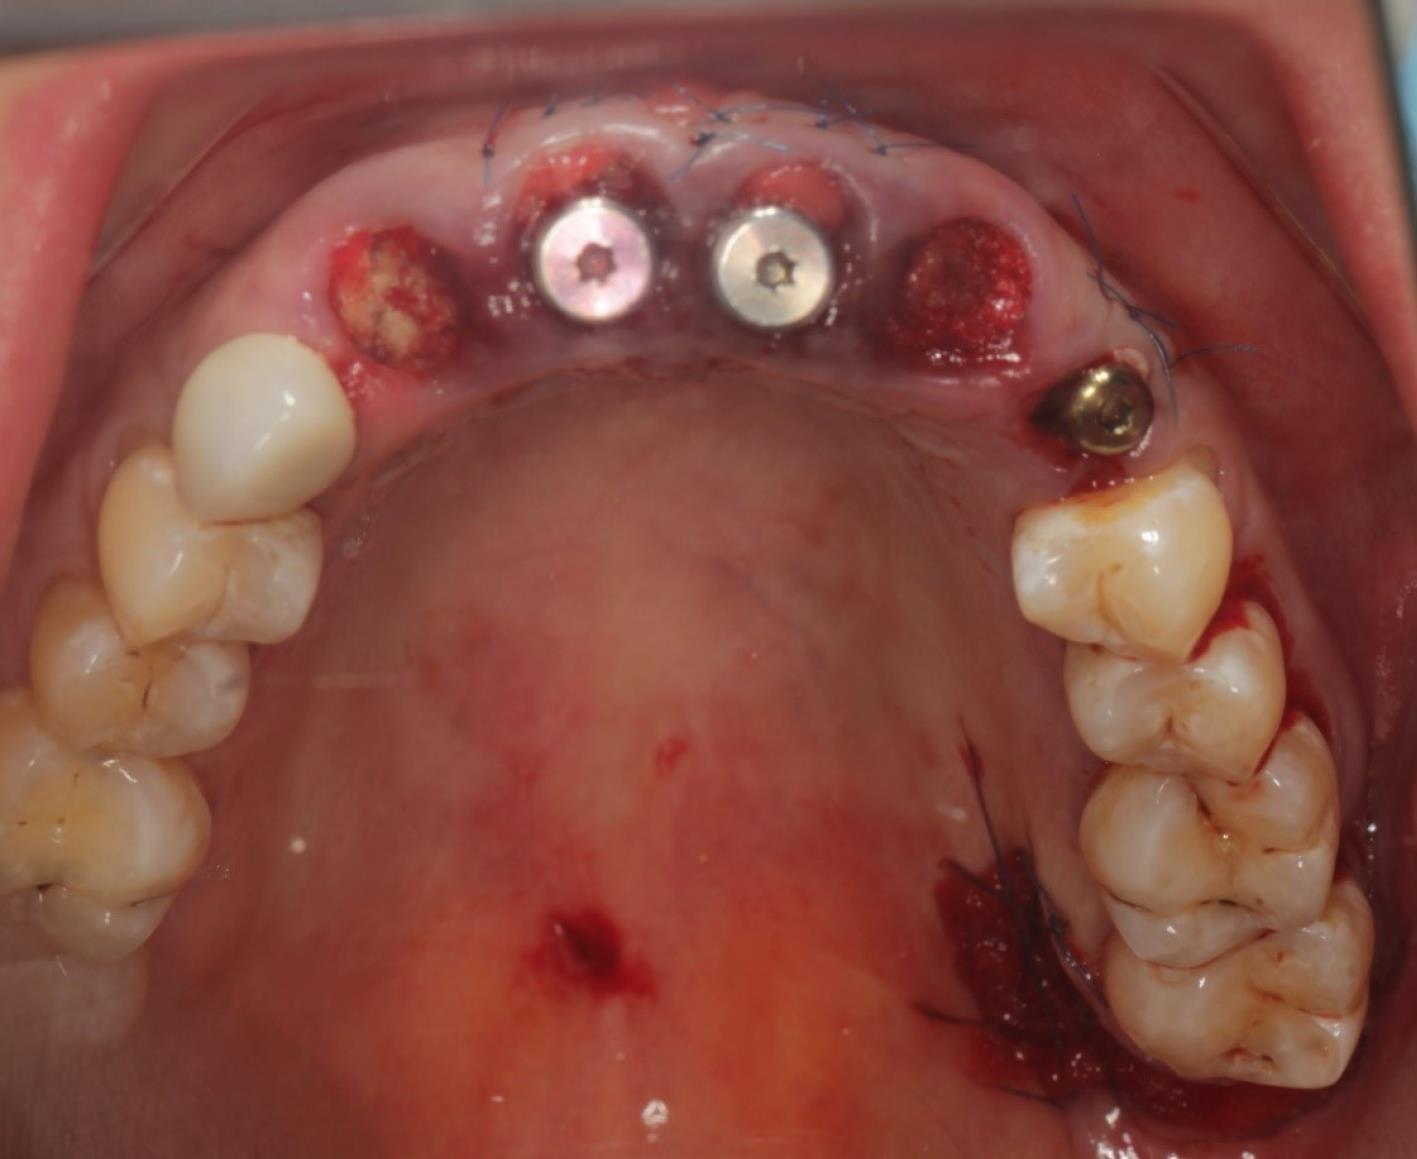

The procedure included three steps: tooth extraction, immediate implant placement, and peri-implant soft tissue surgery with a connective tissue graft from the maxillary tuberosity (Figures 1, 2, 3, and 4). A pocket was formed on the vestibular aspect of the implant to be placed, and its expansion was limited to preserve the integrity of the hard and soft tissues. Implants were placed according to standard surgical protocol with immediate insertion 3 mm apical to the mid-vestibular mucosal plane with a torque of 30, 45, and 55 Ncm. The bone quality of each patient was assessed during the procedure. Primary stability was achieved by virtue of the palatal wall. In the projection of the maxillary tuberosity, a full-thickness 2 × 2‒3-cm connective tissue graft was harvested and de-epithelialized. The soft tissue graft was fixed in the vestibule with interrupted sutures.

Figure 6.

Soft tissue graft